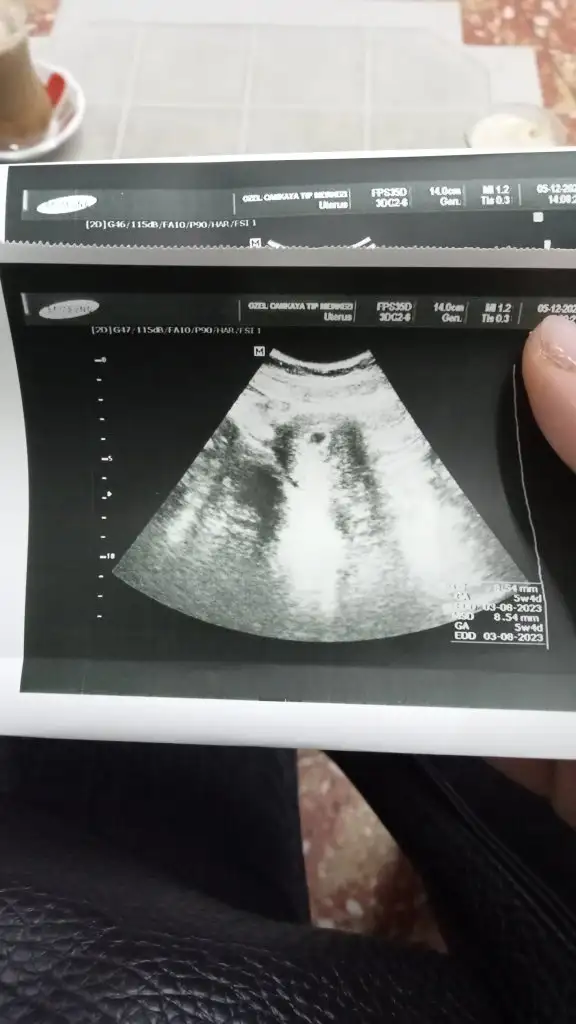

pozitifbiri pozitifbiri canim keseyi gördüm❤️ çok sükür haftasiyla uyumlu bi sıkıntımız yok 19 da kalp atisini duymaya çagırdı darısı diger bekleyen arkadaslarin basina 🥰🥰

img-20221205-wa0002-jpeg.3171844